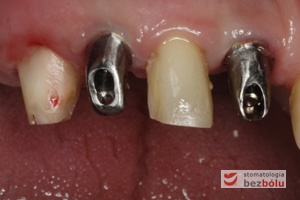

Filary protetyczne przygotowane do pobrania wycisku - transfery wyciskowe typu "bałwanek" przykręcone do implantów - zęby po redukcji dziąsła

Filary protetyczne przygotowane do pobrania wycisku – transfery wyciskowe typu „bałwanek” przykręcone do implantów – zęby po redukcji dziąsła

Transfery wyciskowe - widok z przodu - przenośniki typu "bałwanek" dedykowane pojedynczym implantom

Transfery wyciskowe – widok z przodu – przenośniki typu „bałwanek” dedykowane pojedynczym implantom